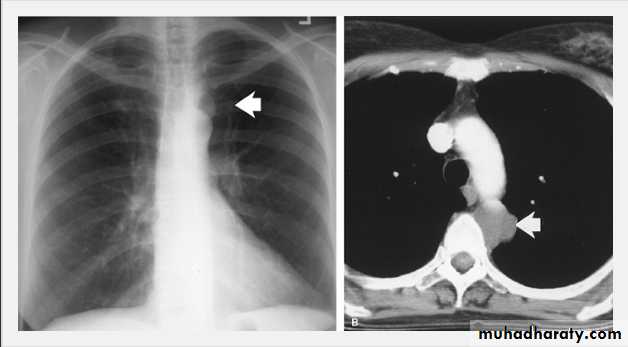

Thymoma.

A chest x-ray (A) reveals an unusual contour over the left hilum (arrows). That the hilum is not obscured (no silhouette sign) indicates that the mass must either be in front of or behind the hilum. A computed tomography scan (B) reveals a soft tissue mass (arrow) just to the left of the aorta. This is the most common location of a thymoma.